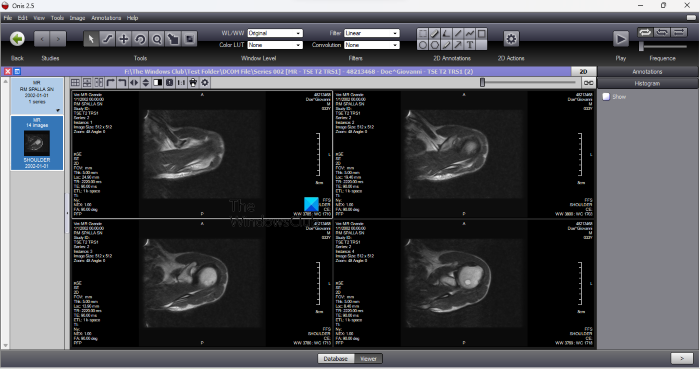

2] Onis

Onis is a DICOM Viewer software that has both free and paid versions. You can download the free version from its website, onis-viewer.com. It has an option to upload all the DICOM files from a particular folder at once. You can also create different albums for DICOM images. To upload the DICOM images, click on the Plus icon on the bottom left side and select the Find DICOM files from a folder option. After that, select the folder containing the DICOM images.

After uploading all the DICOM files, select the Viewer tab to view all the DICOM files. Here, you can perform different actions on your DICOM files. If you have uploaded multiple DICOM files, you can play a slideshow with a particular frequency. Different annotation tools are also available on the Toolbar. You can add text to the DICOM files, draw shapes and free-hand drawings, and measure the distance and angle between two points.

The Export option is also available in the software that lets you export the DICOM files into JPG and BMP image formats.